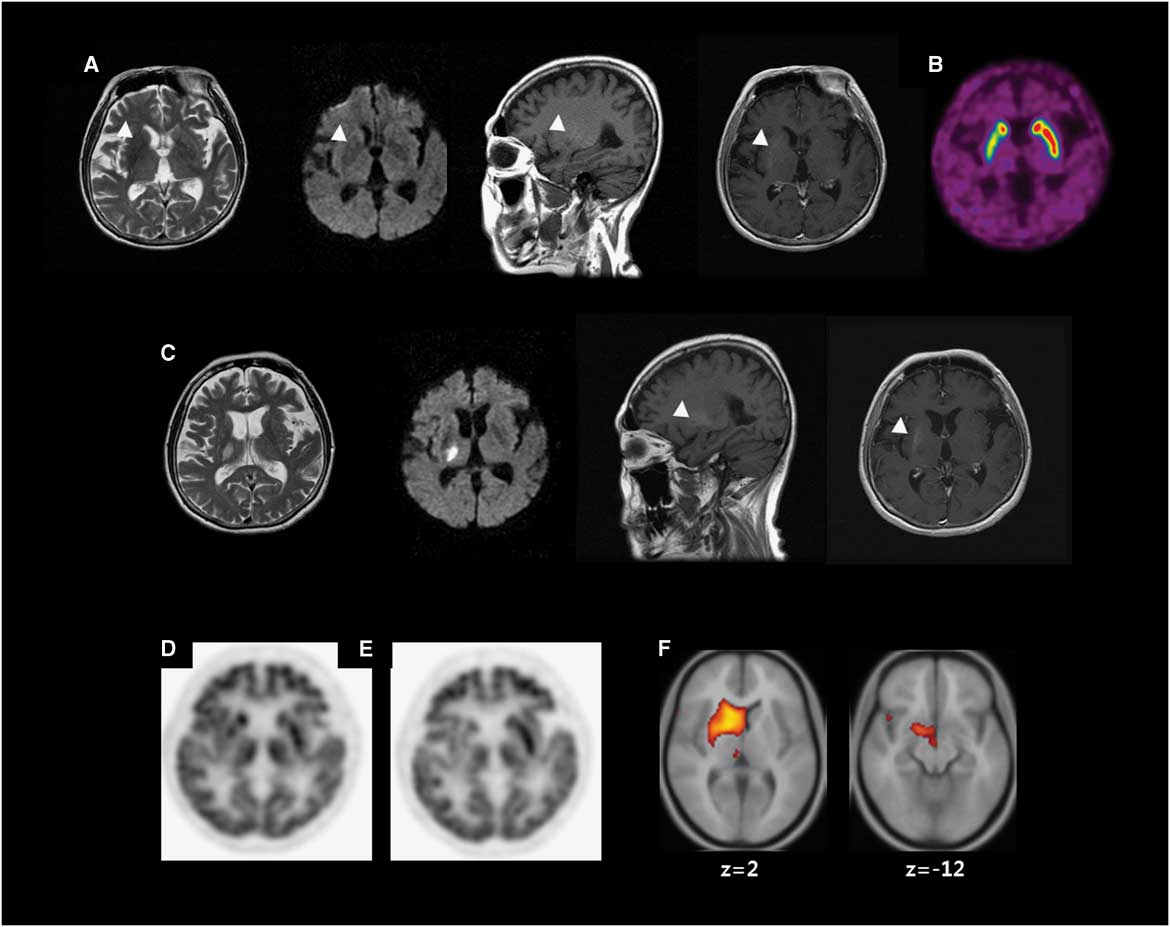

A 62-year-old woman with poorly controlled DM visited our department due to sudden-onset involuntary movements. Her neurological examination (NE) was normal, with the exception of involuntary movements consisting of continuous, irregular, mixed choreic and ballistic movements involving the left face, arm and leg. At admission, her serum glucose was 195 mg/dl and her glycated haemoglobin (HbA1c) 16.2%. MRI showed hypointensities on T2-weighted image, hyperintensities on T1-weighted image and normal diffusion-weighted image in the right putamen (Figure 1A). 18F-fluorodeoxyglucose positron emission tomography (18F-FDG–PET) showed hypometabolism in the right putamen (Figure 1D).

Figure 1 Neuroimaging. (A) Brain MRI at the first presentation of hemichorea shows low signal intensity on T2-weighted image (T2WI), high signal intensity (HSI) on T1-weighted image (T1WI) without (sagittal) or with (axial) gadolinium enhancement and diffusion weighted image (DWI) (arrow heads). (B) 18F-fluorinated N-3-fluoropropyl-2-beta-carboxymethoxy-3-beta-(4-iodophenyl) nortropane (18F-FPCIT) positron emission tomography (PET) shows decreased 18F-FPCIT uptake in the right putamen. (C) The third MRI shows acute infarction in the right thalamus on T2WI and DWI. T1WI without (sagittal) or with (axial) gadolinium enhancement shows persistent HSI in the right putamen (arrow heads). (D) 18F-fluorodeoxyglucose (18F-FDG) PET shows hypometabolism in the right putamen. (E) A follow-up 18F-FDG–PET shows hypometabolism in the right caudate nucleus (CN), putamen and thalamus (54 months after the initial 18F-FDG–PET). (F) Voxel-based subtraction analysis of 18F-FDG–PET shows decreased metabolism of the right CN, putamen, subthalamic area and thalamus in the follow-up scan.

Serum glucose was controlled (HbA1c<7 %). Various drugs including haloperidol and tetrabenazine were ineffective for CB. She showed postural instability after anti-dopaminergic drugs including clozapine. The second MRI showed no new lesions. 18F-fluorinated N-3-fluoropropyl-2-beta-carboxymethoxy-3-beta-(4-iodophenyl) nortropane (18F-FPCIT) PET showed decreased uptake in the right putamen (Figure 1B). Levodopa was effective. Both clozapine and levodopa were tapered, leaving CB as the lone symptom.

She had been followed up for persistent CB for 15 months until sudden-onset left hemiparesis developed. The third MRI showed an acute infarction in the right thalamus (Th) and corona radiata (CR; Figure 1C). NE showed left hemiparesis without sensory deficit. After she recovered from hemiparesis, she remained free of CB.

Three years later, she was hospitalized for coronary heart disease and an appendectomy (HbA1c<7.5%). The hemichorea returned during hospitalization without any suspected drugs. Choreic movements of her left hand were temporarily mixed with dystonia in the early follow-up but became purely choreic later. No new lesion was demonstrated on the fourth MRI. 18F-FDG–PET was repeated and compared with the previous using voxel-based subtraction analysis, demonstrating decreased metabolism in the right subthalamic nucleus (STN), caudate nucleus (CN), putamen and Th (Figure 1E–F).

PET subtraction analysis revealed hypometabolism in the CN and STN. Focal lesions in either the CN or STN have been shown to result in secondary CB. Thus, the recurrence of her hemichorea could be related to STN or CN dysfunction, which could dominate over the beneficial effect of pre-existing Th infarction on her CB. Previously, we suggested that a faulty network for CB had formed during the first episode as a pathologic basis for recurrence in a patient with hypoglycaemic CB.Reference Lee, Lee, Ahn, Hong and Kim 5 Similarly, an aberrant network could have been generated during the initial episode under the influence of the putaminal lesion. This network might have been further modified by an additional thalamic lesion, which was evidenced by a temporary combination of chorea and dystonia. Although the direct mechanism of hypometabolism in the CN and STN was uncertain, this network might consist of structural lesions in the putamen and thalamus and metabolic derangement of the CN and STN. The pathologic network might have been submerged, until it may be relinquished in association with multiple factors such as unstable circulation and surgery.Reference Lee, Lee, Ahn, Hong and Kim 5 The relationship between this hypothetical network and the prolongation of CB remains to be studied.